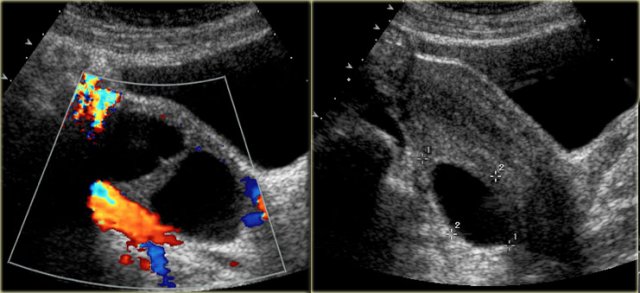

The next case is a transabdominal ultrasound that shows a left-sided multiloculated cystic mass.

This looks like a cystic ovarian neoplasm but no ovary could be identified.

Scroll through the images

CT of the same patient shows a multi-loculated cystic mass adjacent to the bladder, connected to the left ovarian vein (arrow).

There are thick septations and irregular wall thickening.

On the basis of this CT the distinction between a benign ovarian lesion such as as cystadenofibroma and a malignant ovarian lesion cannot be made.

The lesion was resected and found to be a cystadenofibroma.